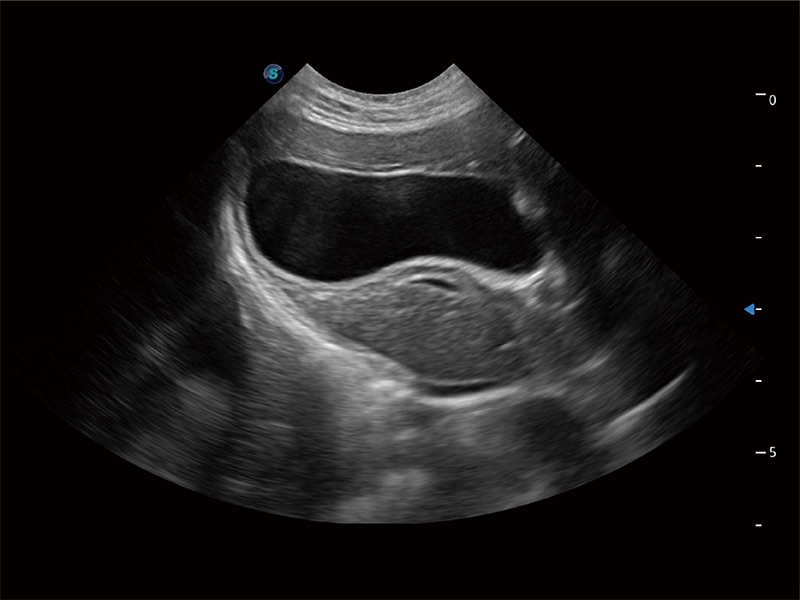

(犬)肝脏

(猫)胆囊